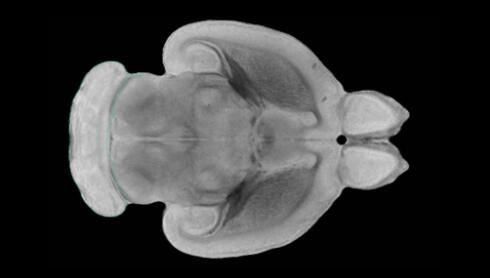

近日,一項刊登在國際雜志Nature上的研究報告中,來自劍橋大學的科學家們通過研究揭示了隨著年齡增長大腦僵硬程度的增加導致大腦干細胞功能異常的分子機制,同時研究者還開發(fā)出了一種新方法能將老化的干細胞逆轉(zhuǎn)回年齡健康狀態(tài);相關研究結(jié)果有望幫助研究人員理解機體大腦的老化過程以及如何開發(fā)治療年齡相關大腦疾病的新型療法。

隨著機體年齡增加,肌肉和關節(jié)都會變得僵硬,這就會使得日?;顒幼兊酶永щy,本文研究表明,我們的大腦也是如此,與年齡相關的大腦僵硬對大腦干細胞的功能或許有著重要影響。文章中,研究人員對年輕和老化大鼠的大腦進行研究闡明了年齡相關大腦僵硬對少突膠質(zhì)前體細胞(OPCs,oligodendrocyte progenitor cells)功能的影響。OPCs是一類對維持正常大腦功能非常重要的大腦干細胞,其對于髓磷脂的再生也非常重要,髓磷脂是神經(jīng)組織周圍的脂肪鞘,在多發(fā)性硬化癥中髓磷脂的再生常常會被損傷,機體老化對這些細胞的影響常常會誘發(fā)多發(fā)性硬化癥的發(fā)生,這些細胞的功能在老化的健康人群中同樣會下降。

為了確定老化OPCs的功能缺失是否可以被逆轉(zhuǎn),研究人員將來自老化大鼠機體的老化OPCs轉(zhuǎn)移到了年輕大鼠柔軟的海綿狀大腦組織中去,值得注意的是,這些老化的大腦細胞能夠重新恢復活力,其行為非常像年輕更加強壯的細胞。這項研究中,研究人員在實驗室中開發(fā)出了具有可變僵硬程度的新型材料,并在受控環(huán)境下研究這些材料的生長及其對大鼠大腦干細胞的影響,這些材料能被工程化改造具有和年齡或老化大腦相似的柔軟程度。

為了深入理解大腦組織柔軟和僵硬影響細胞行為的分子機制,研究人員對細胞表面一種名為Piezo1的蛋白質(zhì)進行了分析,該蛋白質(zhì)能“告知”細胞其周圍的環(huán)境為柔軟或僵硬。研究者Kevin Chalut說道,我們發(fā)現(xiàn),當在僵硬材料上促進年輕具有功能性的大鼠干細胞時,這些細胞就會表現(xiàn)出功能異常,并失去其再生的能力,實際上其行為與老化細胞相似。當將老化的大腦細胞在柔軟材料上生長時,其功能就會表現(xiàn)得像年輕細胞一樣,換句話說,其能夠重新恢復年輕的活力。

當研究者從老化大腦干細胞的表面剔除Piezo1蛋白后,他們就能夠誘騙細胞感知柔軟的周圍環(huán)境,甚至當將細胞在僵硬材料上生長時也是如此。此外,當在老化大鼠大腦中剔除OPCs上的Piezo1時,就會促進細胞變得年輕并再次承擔正常的再生功能。研究者Susan Kohlhaas表示,多發(fā)性硬化癥是一種痛苦讓患者致殘的疾病,隨著時間推移,我們迫切需要開發(fā)出減緩并抑制患者殘疾的新型療法。這項研究中,研究人員闡明了大腦干細胞老化的分子機制,以及如何通過逆轉(zhuǎn)該過程來實現(xiàn)恢復大腦干細胞活力,后期研究人員將會基于本文研究開發(fā)出新型療法來治療多種與老化和多發(fā)性硬化癥相關的疾病,包括如何潛在恢復大腦失去的功能等。